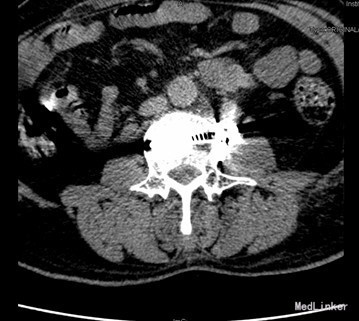

查体:腰4、5棘突轻度叩压痛,双侧大腿后外侧小腿外侧及足背感觉功能减退,以右侧明显。 辅查:CT示腰4椎体骨质破坏并增生、硬化改变,以骨质破坏为主,左侧椎旁软组织肿块形成,结核?肿瘤待排。腰4、5腰5骶1椎间盘突出。腰椎退行性变。MRI示腰4椎体骨质破坏,性质?腰4、5腰5骶1椎间盘突出,腰椎退行性变,双侧髂骨信号不均匀,性质?

初步诊断:腰4椎体骨质破坏:结核?肿瘤? 诊疗计划:经前路腰4椎体部分切除,椎管减压,取自体髂骨植骨融合,Antares内固定术

术中见腰4椎体骨质破坏,其内可见空腔形成,周围骨质硬化,左侧椎旁椎体空腔内可见少量干酪样坏死组织,腰3、4椎间盘破坏、碎裂,部分组织突入椎管,压迫硬膜囊,取坏死组织术中冰冻切片示:肉芽肿性炎症伴坏死。